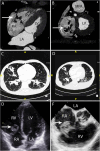

Infective Endocarditis (IE) remains a significant health challenge. Despite an increasing awareness, mortality is high and has remained largely unchanged over recent decades. Early diagnosis of IE is imperative and to assist clinicians several diagnostic criteria have been proposed. The best known are the Duke criteria. Originally published in 1994, these criteria have undergone significant modifications. This manuscript provides a timeline of the successive changes that have been made over the last 30 years. Changes which to a large degree have reflected both the evolving epidemiology of IE and the proliferation and increasing availability of advanced multi-modality imaging. Importantly, many of these changes now form part of societal guidelines for the diagnosis of IE. To provide validation for the incorporation of cardiac computed tomography (CT) in current guidelines, the manuscript demonstrates a spectrum of pictorial case studies that re-enforce the utility and growing importance of early cardiac CT in the diagnosis and treatment of suspected IE.